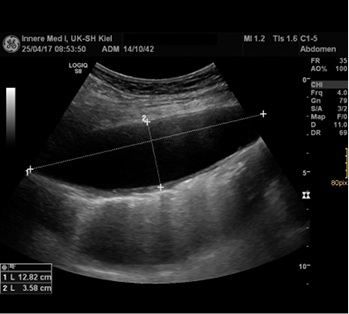

In der Sonographie des linksseitigen Thorax stellte sich die Raumforderung als schmalovale liquide Formation zwischen Lungen- und Thoraxwand dar, die durch eine feste Kapsel abgeschlossen war (Größe ca. 14 × 3,8 cm).

Zwei Monate später wurde die ehemalige Punktionsstelle am linken Thorax sonographisch kontrolliert. Es wurde erneut eine Flüssigkeitsansammlung im Pleuraspalt in einer Größe von 12,5 × 3,8 cm festgestellt (  Abb. 5 ).